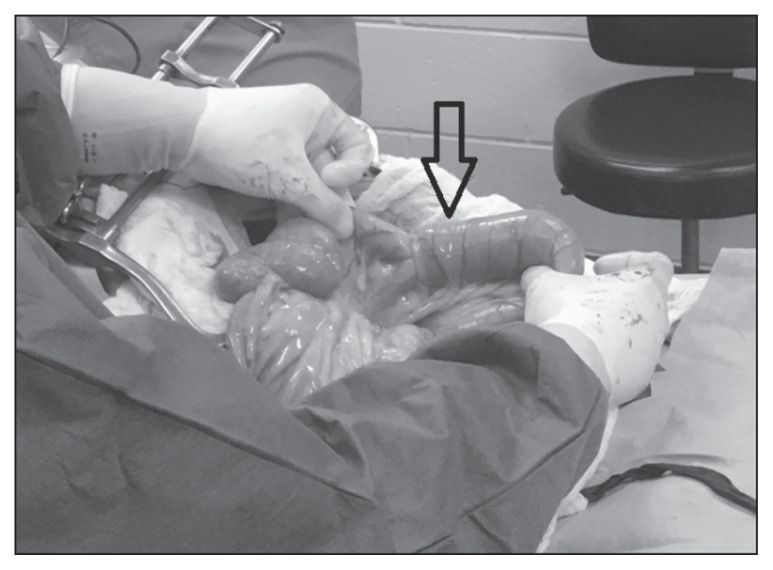

Figure 4. Intraoperative photograph showing an intussusception at exploratory laparotomy, demonstrating the telescoped segment of bowel prior to surgical correction.

| Manual Reduction | Recent intussusception with viable bowel; minimal adhesions; reducible segment | Gentle milking of intussuscipiens away from intussusceptum (NEVER pull on intussusceptum); assess bowel viability post-reduction |

| Resection and Anastomosis | Non-reducible intussusception; non-viable bowel; adhesions present; neoplasia; majority of cases (84%) | Remove affected segment; end-to-end anastomosis with sutures (absorbable monofilament) or staples |

Assessment of bowel viability is critical. Signs of viable bowel include: pink color, presence of peristalsis, pulsatile mesenteric vessels, and return of color after decompression. Non-viable bowel appears dark purple/black, lacks peristalsis, and has no mesenteric pulses - these segments require resection.

Figure 4 - Intraoperative photograph of double jejunoileal intussusception through ileocolic orifice prior to surgical correction (Case 1): Aprea F et al. (2012). Can Vet J. Figure 3. PMC3398523. URL: https://pmc.ncbi.nlm.nih.gov/articles/PMC3398523/ - Open Access.